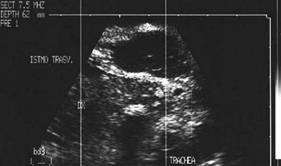

Lobul drept, proiectie trasversala si longitudinala.

Femeie de 29 ani. Nodul de consistenta dura in lobul

drept si istm.

Ecografia: nodul cu margini difuze in lobul drept si istm, care deformeaza

conturul anterior al glandei, structura parenchimatoasa, neoomogena, hipoecogena.

Prezenta de linfonoduli laterocervicali.

Citoaspiratia: carcinom papilar.

Examen histologic: carcinom papilar plurifocale varianta foliculara.